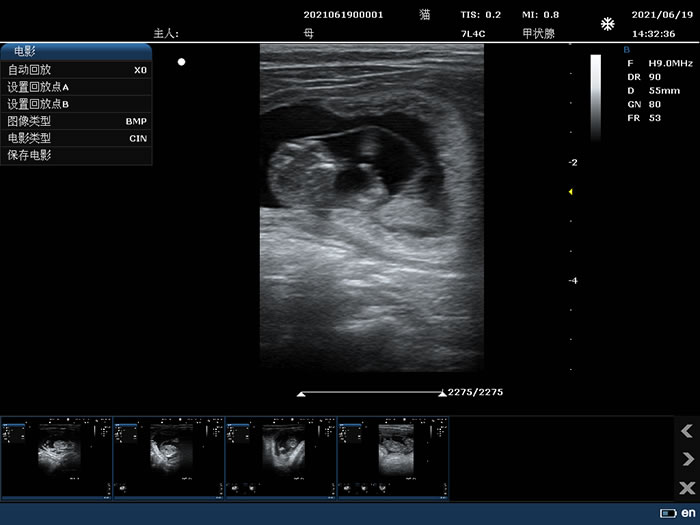

7L4C: 7.5MHz/L38mm/128,Convex array probe

Thyroid

7L4C: 7.5MHz/L38mm/128,Convex array probe

Thyroid